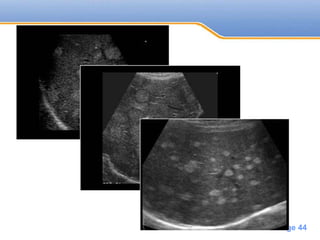

Ultrasound

Hypoechoic metastasis

• Lymphoma

• Sarcoma

• Most adenocarcinoma(breast, lung, pancreas)

Hyperechoic

• Colorectal carcinoma and other GIT

• Carcinoid, Renal cell carcinoma, islet cell

tumor

• #43 Hypoechoic liver metastases of a colon carcinoma Hypoechoic liver metastases of a melanoma

• #45 Liver metastasis of a colon carcinoma with a hyperechoic lesion in the left liver lobe with a halo.